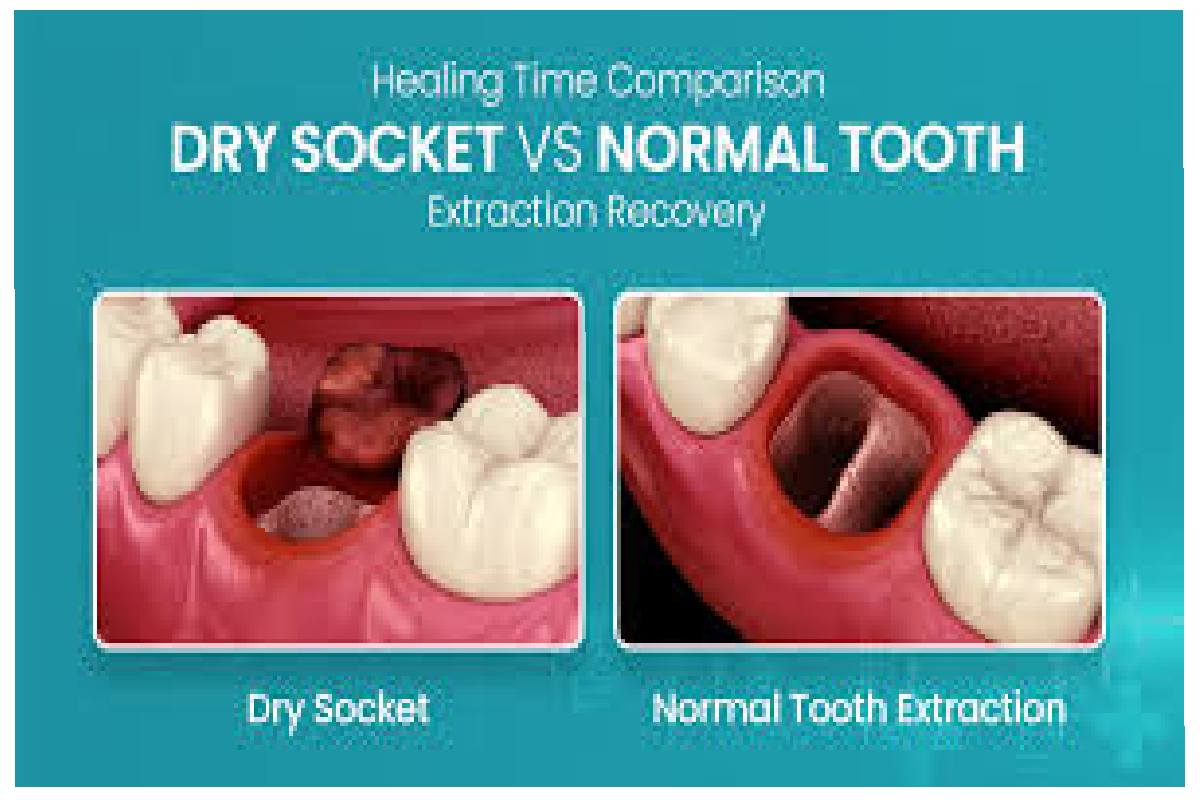

Comparing Pictures of pictures of dry socket vs normal healing

Normal Healing

- Appearance: The socket is filled with a black blood clot, which may whiten or turn yellow as the wound heals.

- Surrounding Tissue: Gingiva: Bright pink with very mild red coloration is possible.

- No Exposed Bone: The clot covers the extraction site to the brim and is wholly formed.

Dry Socket

- Appearance: An empty eye socket or an absence of an eye socket with the bone visible.

- Surrounding Tissue: Swelling, erythema, and inflammation of the gum.

- Signs of Infection: A dry socket may be associated with pus, swelling, or a foul smell.

Why Pictures Are Helpful: It also helps to compare photos of the condition of a dry socket vs. standard healing. In any case, always seek advice from your dentist.